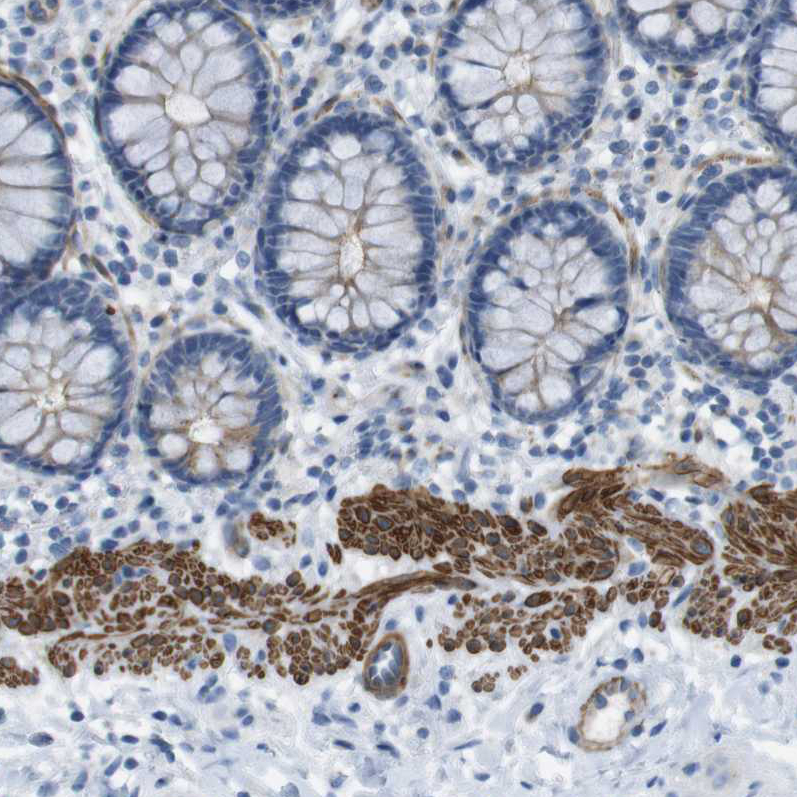

Immunohistochemical staining of human prostate shows strong cytoplasmic positivity in smooth muscle cells.